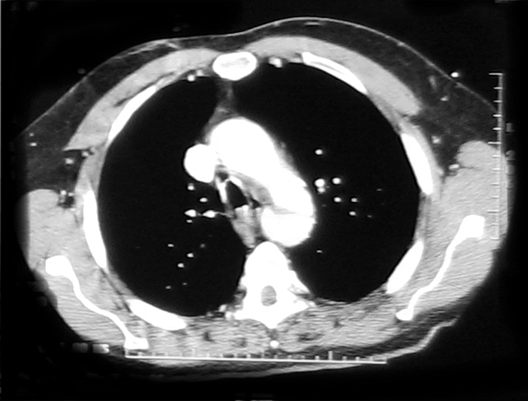

Informed consent was obtained and the patient was offered endovascular repair of the contained aortic rupture using the Medtronic Talent endoprosthesis through a single institution Investigator Investigational Device Exemption (IDE) approved by the FDA. In the endovascular suite, the patient was placed in supine position and underwent local anesthesia with sedation. The left common femoral artery was exposed and then accessed using an 18-gauge needle and a 0.035 inch flexible-tipped Bentson Starter guidewire was passed in a retrograde fashion into the descending aorta under fluoroscopic guidance. 3000U of Heparin was administered and a 14-Fr introducer sheath was placed in the left common femoral artery. The IVUS (Volcano Visions, PV 8.2 F) catheter was used to guide and advance the Starter guidewire safely across the contained rupture area into ascending aorta. Upon advancement of the IVUS probe into the thoracic aorta, the area of transection was encountered. There was a dissection flap with a dilated and disrupted area in the middle of aorta

| Figure 3: IVUS showing the site of aortic rupture. |

(Figure 3). The proximal aspect of the transection was 1.5 cm below the origin of the left subclavian artery. Origins of the arch vessels were marked on the masked picture on the fluoroscopy monitor. Using the IVUS, the aortic diameter was measured 28 mm just distal to the left subclavian artery and 29 mm at origin of the left common carotid artery. It was decided to cover the left subclavian artery to get an adequate landing zone for the endoprosthesis. Therefore, the IVUS was placed just distal to the left carotid artery and its position marked on the fluoroscopic screen. The catheter was then withdrawn until above, and then below the transected area. These measured 36 mm and 76 mm in length, respectively. With these measurements in mind, a 30 mm diameter by 130 mm in length Medtronic Talent device with 15 mm proximal wire configuration was selected to exclude the transected portion of the aorta.